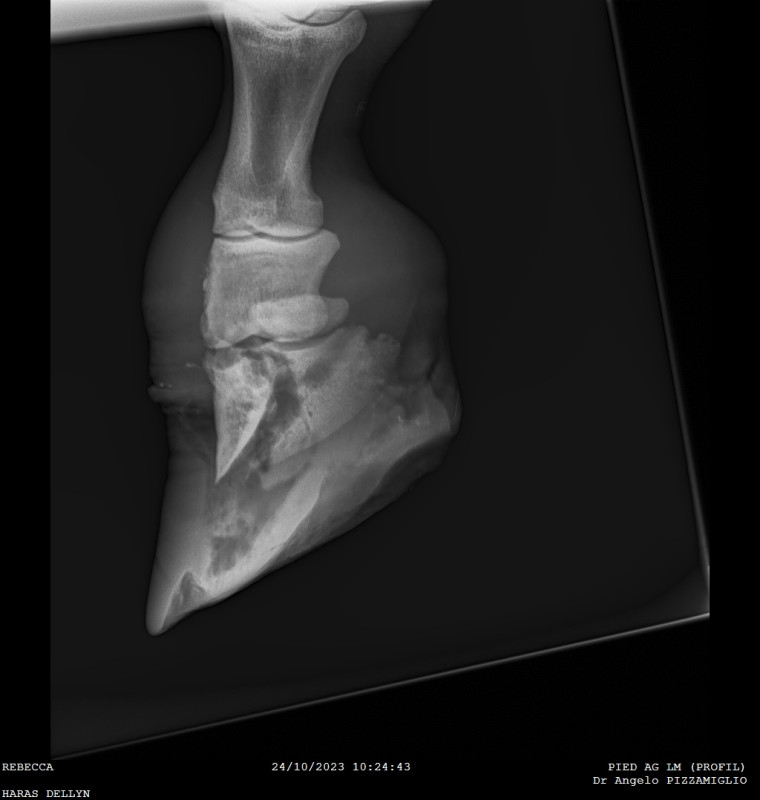

Dans les nouvelles (mauvaises ? Bonnes ? Je ne savais pas, d'où la nouvelle !) l'antibiogramme est revenu. Une bactérie particulièrement coriace. Bien entendu résistante a tout les antibio reçu jusque là. (Pénicilline, Baytril, Marboxyl). Vu le coût en antibio déjà dépensé et le temps perdu, c'est un petit coup dur. Mais bon, à priori l'Ecxenel devrait terrasser la chose. On doit vérifier avec le laboratoire demain.